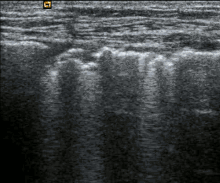

L'échographie pleurale permet de visualiser la paroi thoracique, la plèvre, et le parenchyme pulmonaire[3].